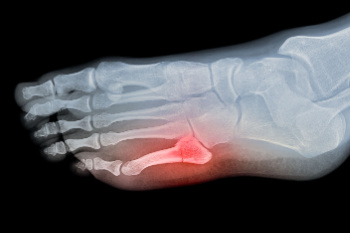

Types of 5th Metatarsal Fractures

A fracture of the 5th metatarsal, the long bone on the outside of the foot that connects to the little toe, can occur in several locations and patterns. One common type is an avulsion fracture, where a tendon or ligament pulls off a small piece of bone near the base of the metatarsal. Another type is a Jones fracture, which occurs slightly farther along the base, and is known for slower healing due to limited blood flow in that region. Additionally, a dancer’s fracture is an oblique break through the shaft of the bone, often caused by twisting or an awkward landing. These 5th metatarsal injuries typically result in pain, swelling, bruising, and difficulty walking. Proper diagnosis with imaging is important to distinguish between the types, as each can require a different treatment approach. A podiatrist can evaluate the extent of the injury and recommend immobilization or surgery, when necessary. If you believe you may have fractured a bone in your foot, it is suggested that you schedule an appointment with a podiatrist for an exam and appropriate treatment solutions.

Broken Foot Causes, Symptoms, and Treatment

A broken foot is caused by one of the bones in the foot typically breaking when bended, crushed, or stretched beyond its natural capabilities. Usually the location of the fracture indicates how the break occurred, whether it was through an object, fall, or any other type of injury.

Common Symptoms of Broken Feet:

- Bruising

- Pain

- Redness

- Swelling

- Blue in color

- Numbness

- Cold

- Misshapen

- Cuts

- Deformities

Those that suspect they have a broken foot shoot seek urgent medical attention where a medical professional could diagnose the severity.

Treatment for broken bones varies depending on the cause, severity and location. Some will require the use of splints, casts or crutches while others could even involve surgery to repair the broken bones. Personal care includes the use of ice and keeping the foot stabilized and elevated.